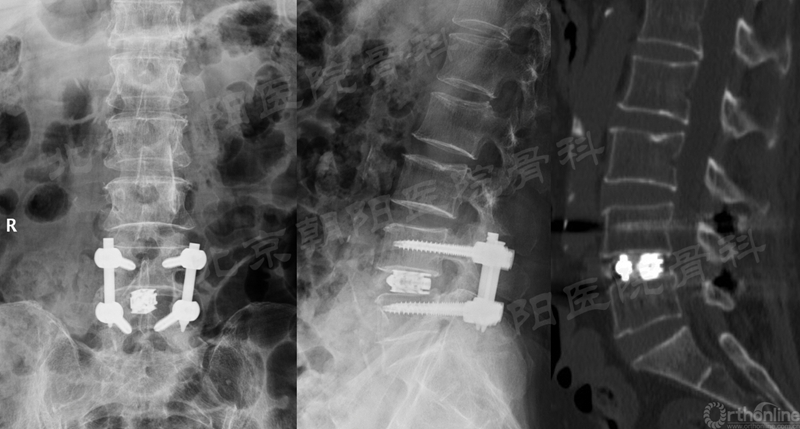

术后X线片与CT(矢状面)

术前、术后MRI及CT(轴位)